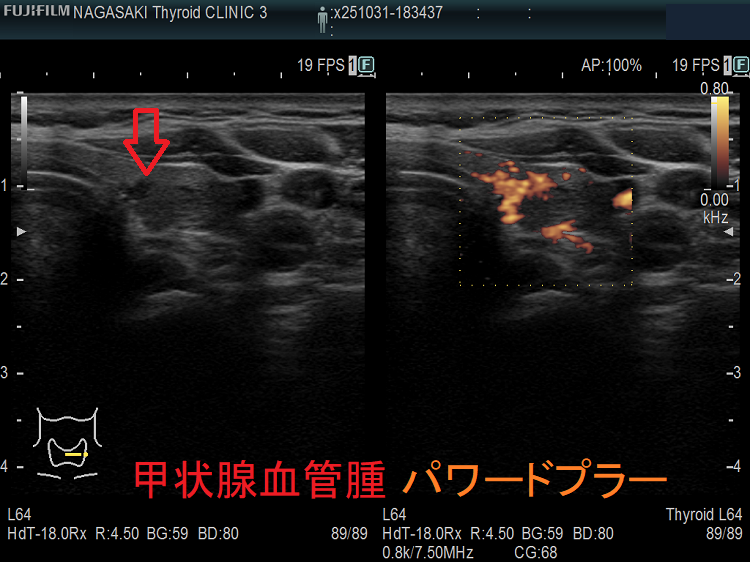

甲状腺に発生する血管腫は非常に稀で、日本の報告例もわずかです(日臨外会誌 72(3),579―583,2011)。

ケース①

ケース②

ケース③

甲状腺血管腫(拡大) ドプラーモード(eFlow);腫瘍内血管が3次元的に見え、毛玉の様。

ケース④